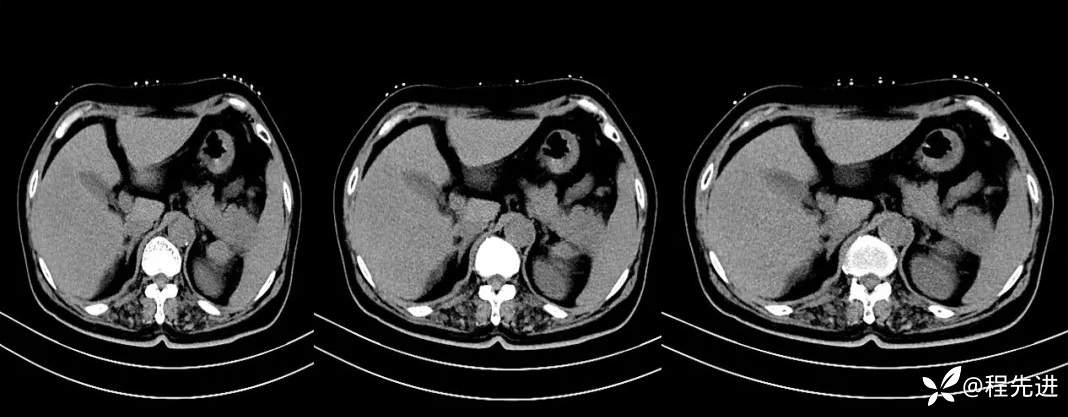

【现病史及既往史】:体检发现胰尾部肿块4年,当时手术病理提示异常增生性病变,现发现右侧顶部包块,逐渐增大,无明显感觉不适

影像检查: